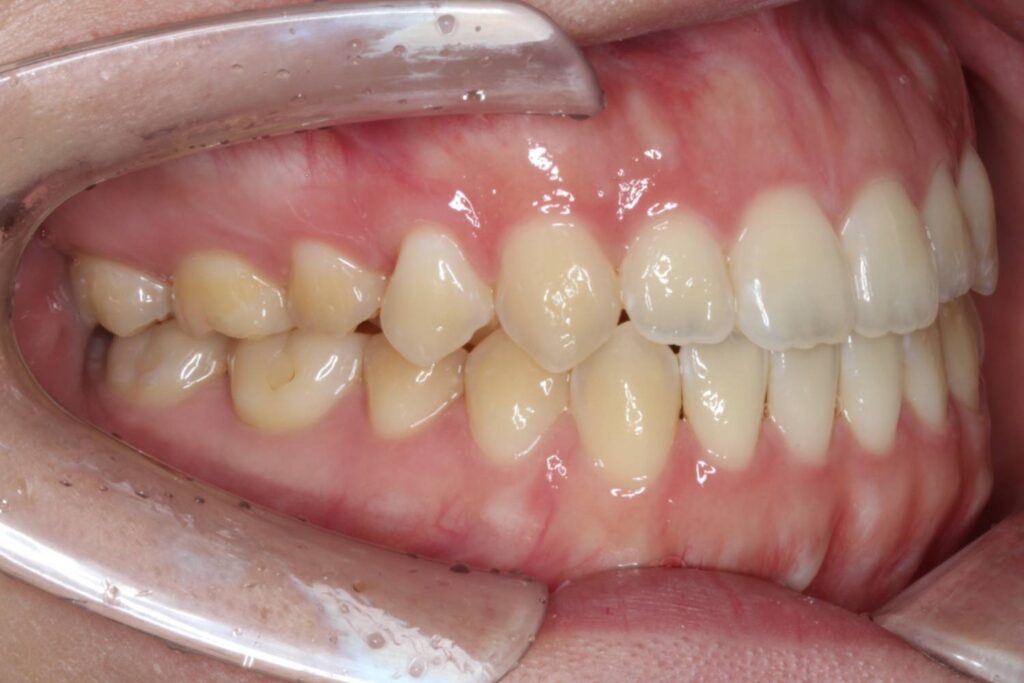

噛み合わせた際、上下顎の前歯が垂直的に被さらず空間ができている、「開咬」という歯並びの状態になっています。

Before